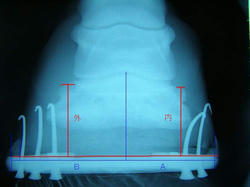

9月の右前肢

今回の右前肢

こちらも蟻洞がなくなりました。

順調に改善しているのが確認できて本当にホッとしました〜